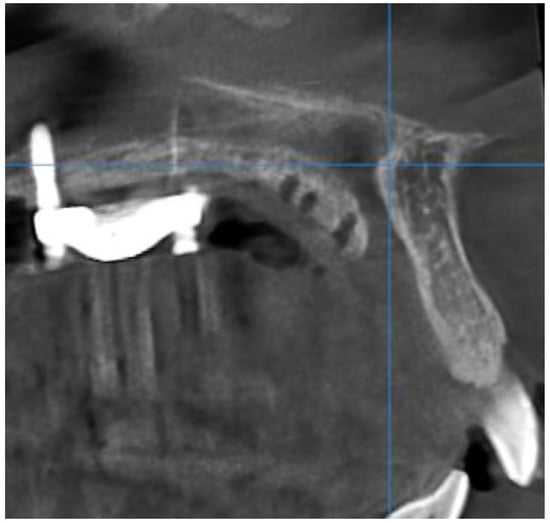

- Stage D or E palatal fusion (as seen in Angelieri et al. [18]) confirmed on CBCT prior to MARPE insertion;